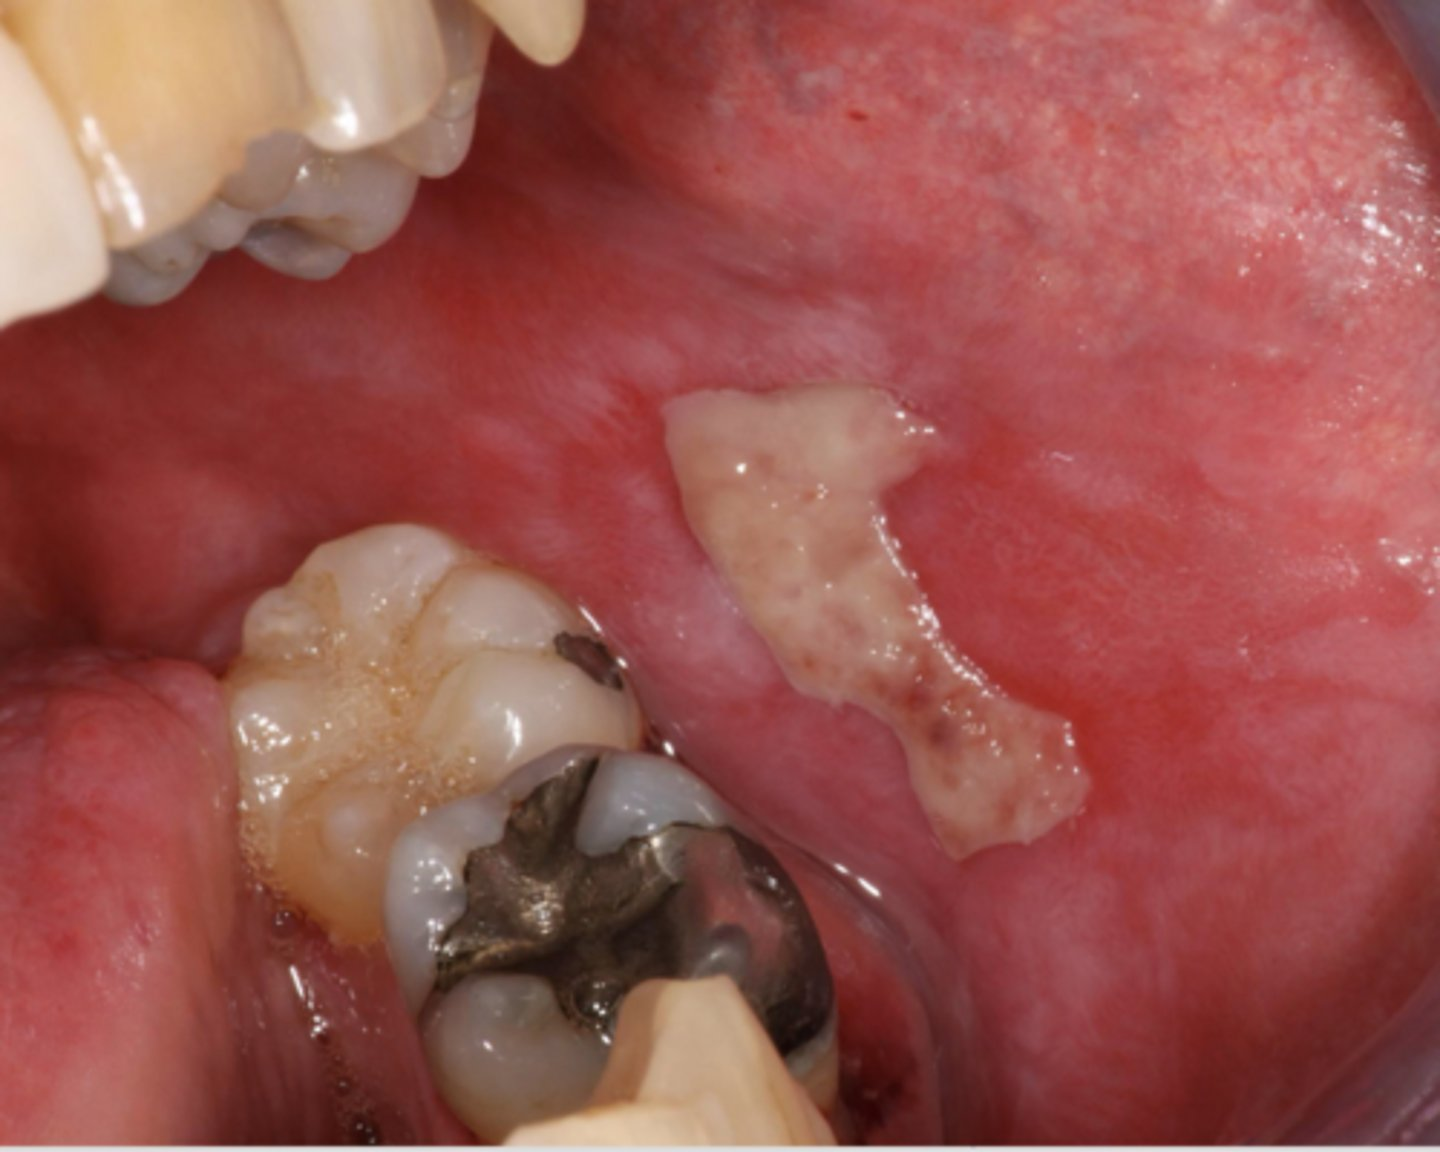

lichen planus (ulcerative and some reticular and erythematous seen)

What condition?